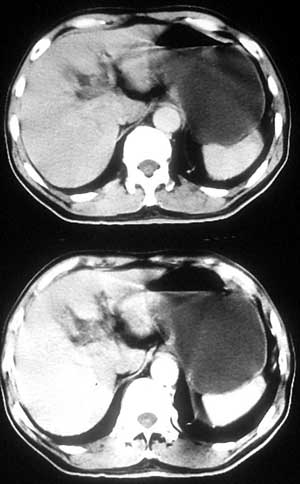

患者,男,57岁,梗阻性黄疸10余天。

这个病例胰头无明显增大,胆总管扩张明显而肝内胆管扩张更不明显,病程较短,

注意到十二指肠乳头明显突出,但尚光滑。分析以下可能性:

1、十二指肠乳头本身的病变,如乳头炎症;

2、急性乳头水肿,胆总管下端结石排石后乳头水肿;

3、壶腹部胆总管下端肿瘤累及十二指肠乳头。

十二指肠乳头粘膜慢性非特异性炎症